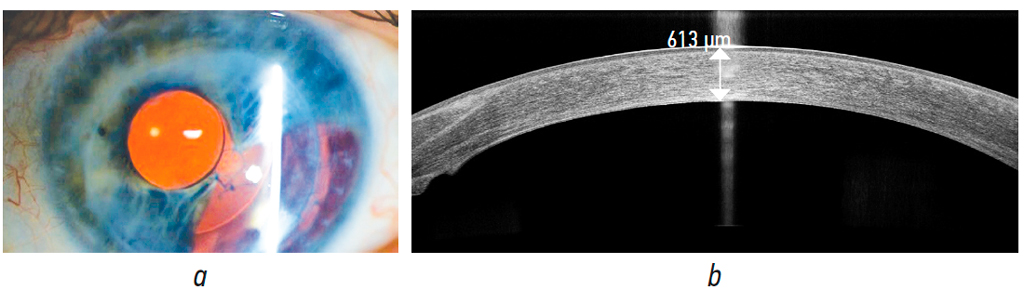

At postoperative month 24, the penetrating graft remained transparent (Fig. 6, a), and BCVA was 0.16. Central corneal thickness based on OCT data was 613 μm (Fig. 6, b). ECD was 873 cells/mm²; IOP was 19 mmHg on hypotensive therapy (brinzolamide + timolol).

Fig. 6. Clinical case No. 1, 24 months after the modified transplantation of the endothelium on descemet membrane with a banded stromal flap: a, photo of the anterior segment of the eye, the pupillary model of hydrophilic IOL is transparent; b, OCT of the cornea, the central thickness of the penetrating graft is 613 µm

Рис. 6. Клинический случай № 1, через 24 мес. после модифицированной трансплантации эндотелия с десцеметовой мембраной с бандажным стромальным лоскутом: a — фото переднего отрезка глаза, сквозной трансплантат роговицы прозрачный, зрачковая модель гидрофильной интраокулярной линзы прозрачная; b — ОКТ роговицы, центральная толщина сквозного трансплантата 613 мкм